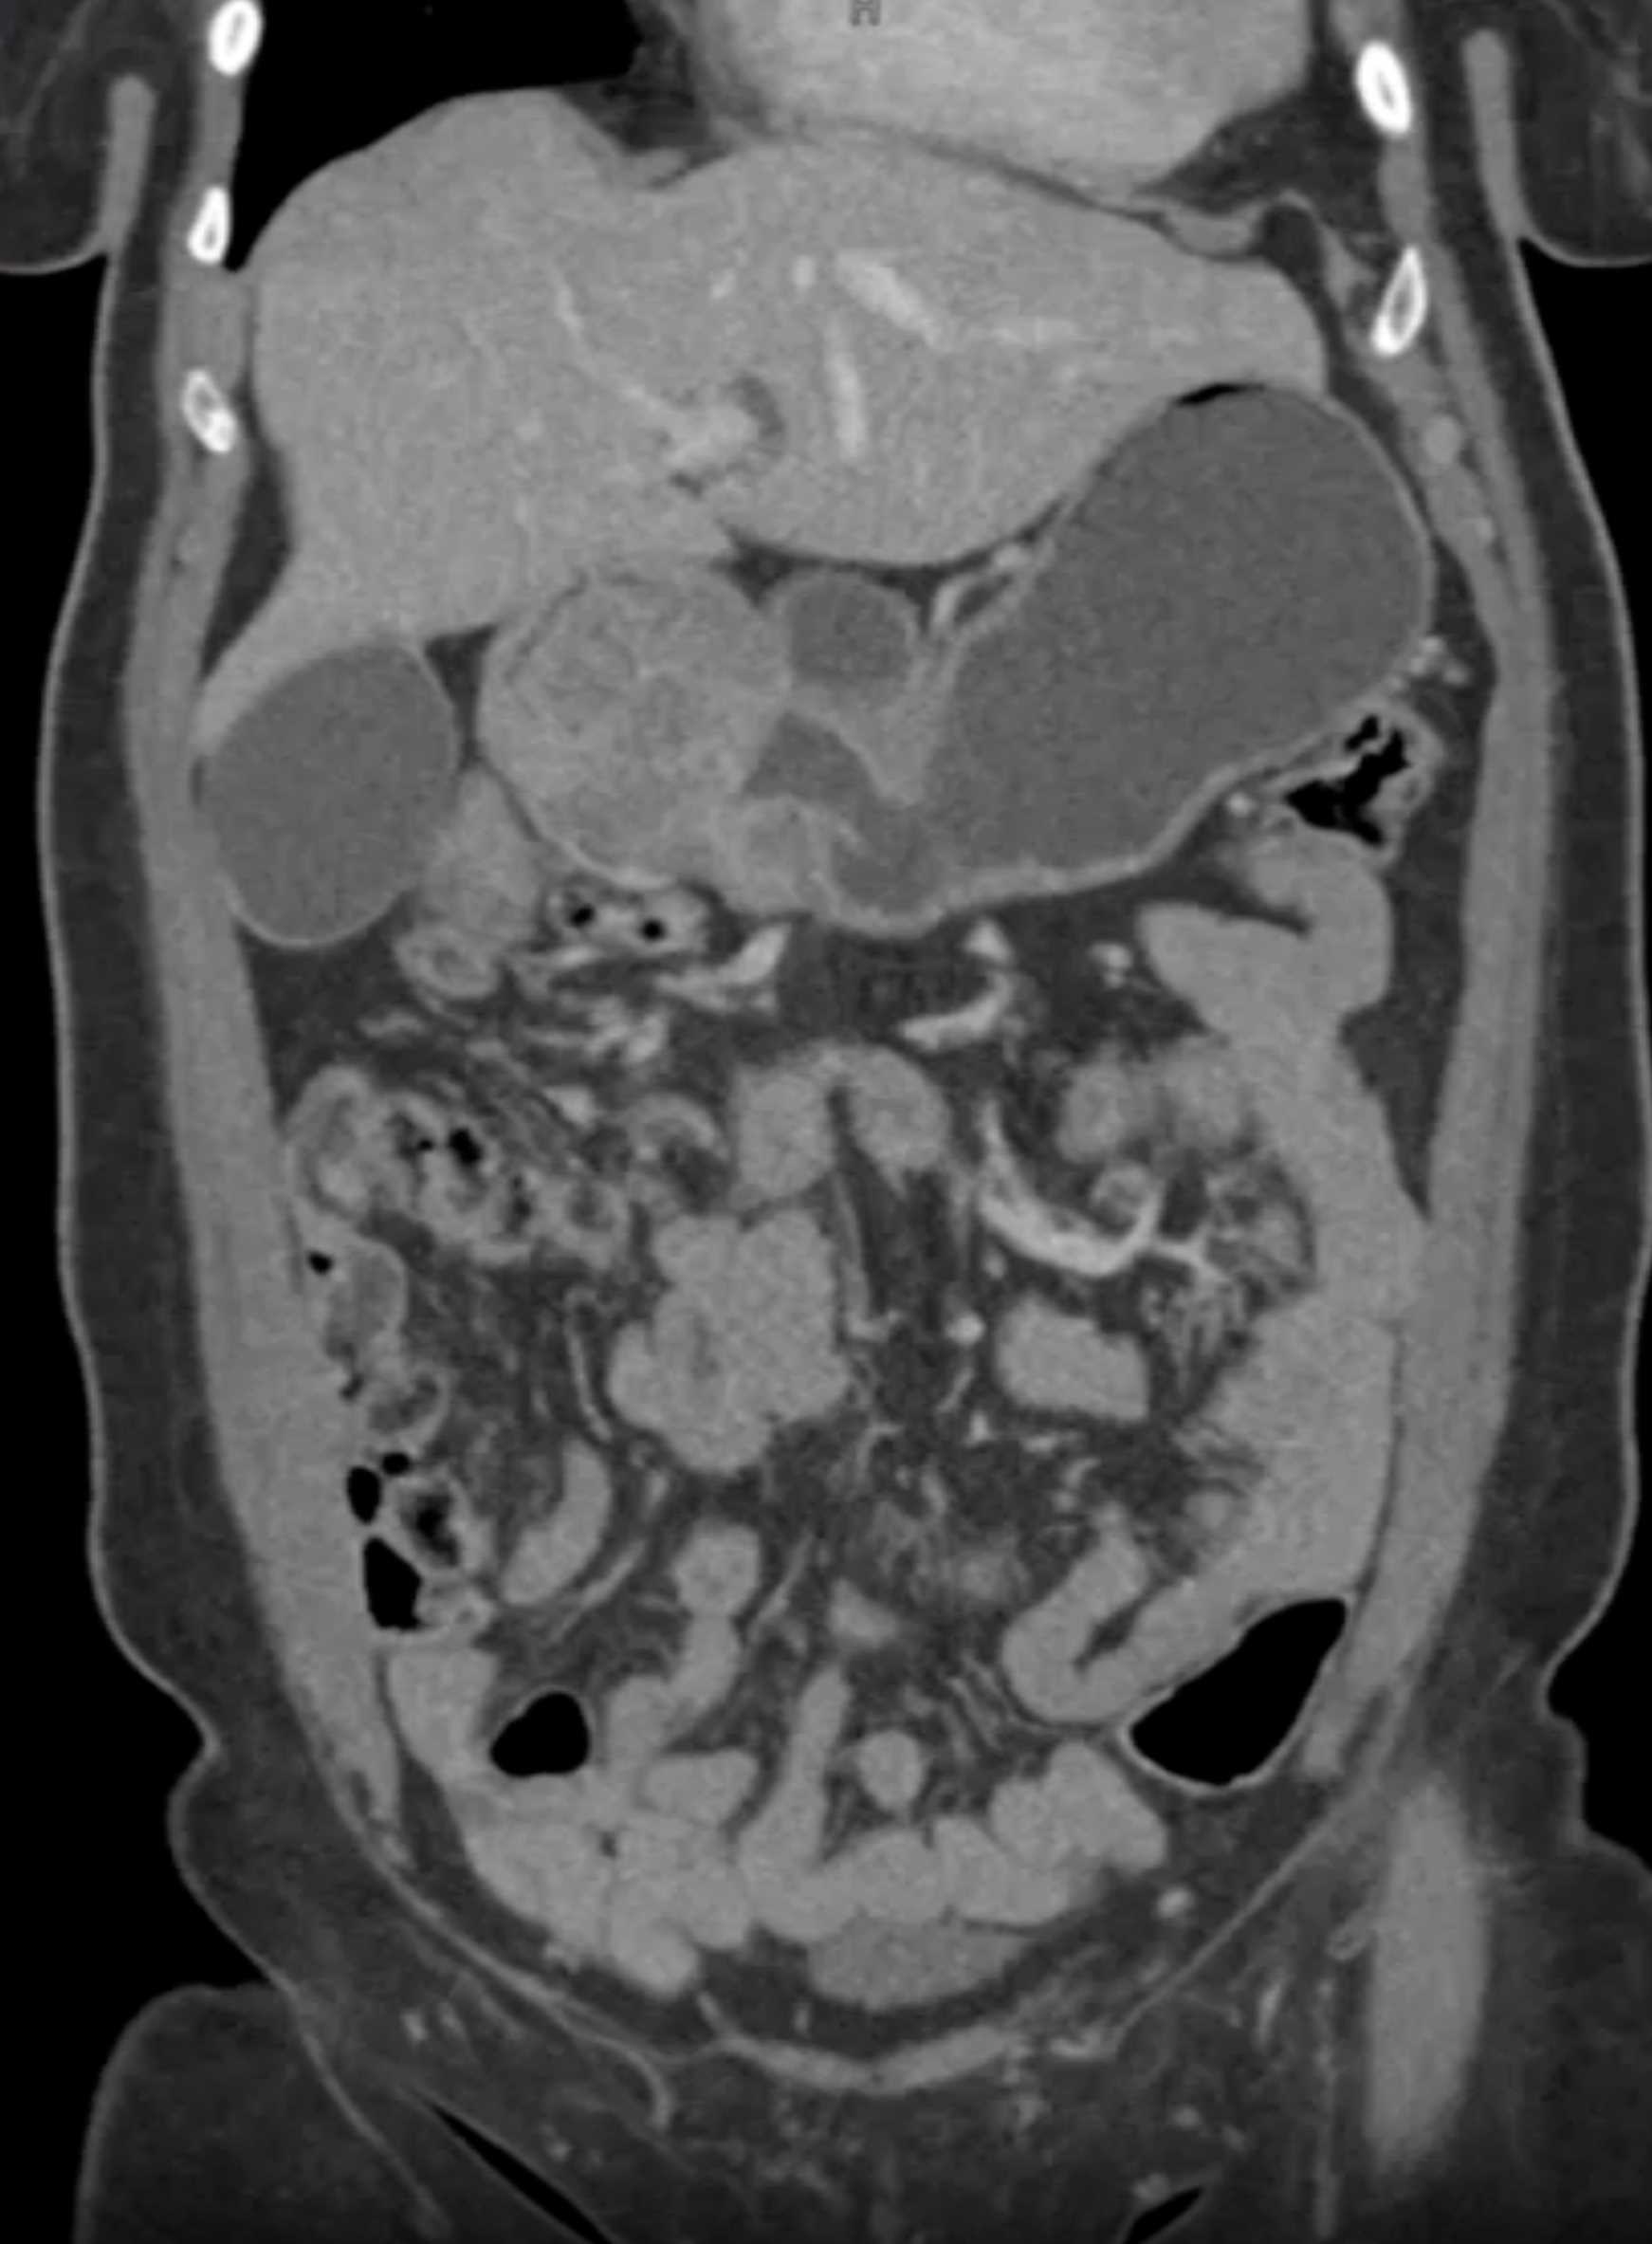

Lagre Gastric GIST Tumor